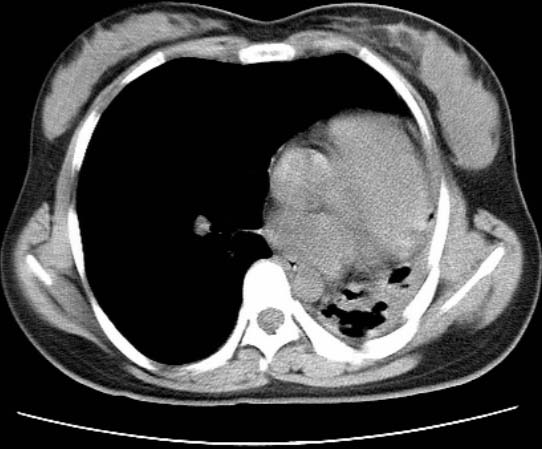

标题: CT25648:求教:是肺发育不全还是结核?

女  20岁。一月前咳血,诊“肺结核”抗痨治疗一月后,咳血停止,现复查。病人精神好。前后ct片对比未见明显变化。既往体检“正常”

1)考虑左肺结核并肺不张、支气管扩张。2)纵隔疝。

以前体检正常只能考虑左肺结核并肺不张、支气管扩张。2)纵隔疝。

考虑左肺结核,左肺毁损,纵膈左偏,既往体检正常不可靠,tb一个月也不会这个样子的,有钙化,应该病程较长,冰冻三尺非一日之寒!

考虑左肺结核,左肺毁损,纵膈左偏,既往体检正常不可靠,tb一个月也不会这个样子的,有钙化,应该病程较长,冰冻三尺非一日之寒

结核,左肺毁损。